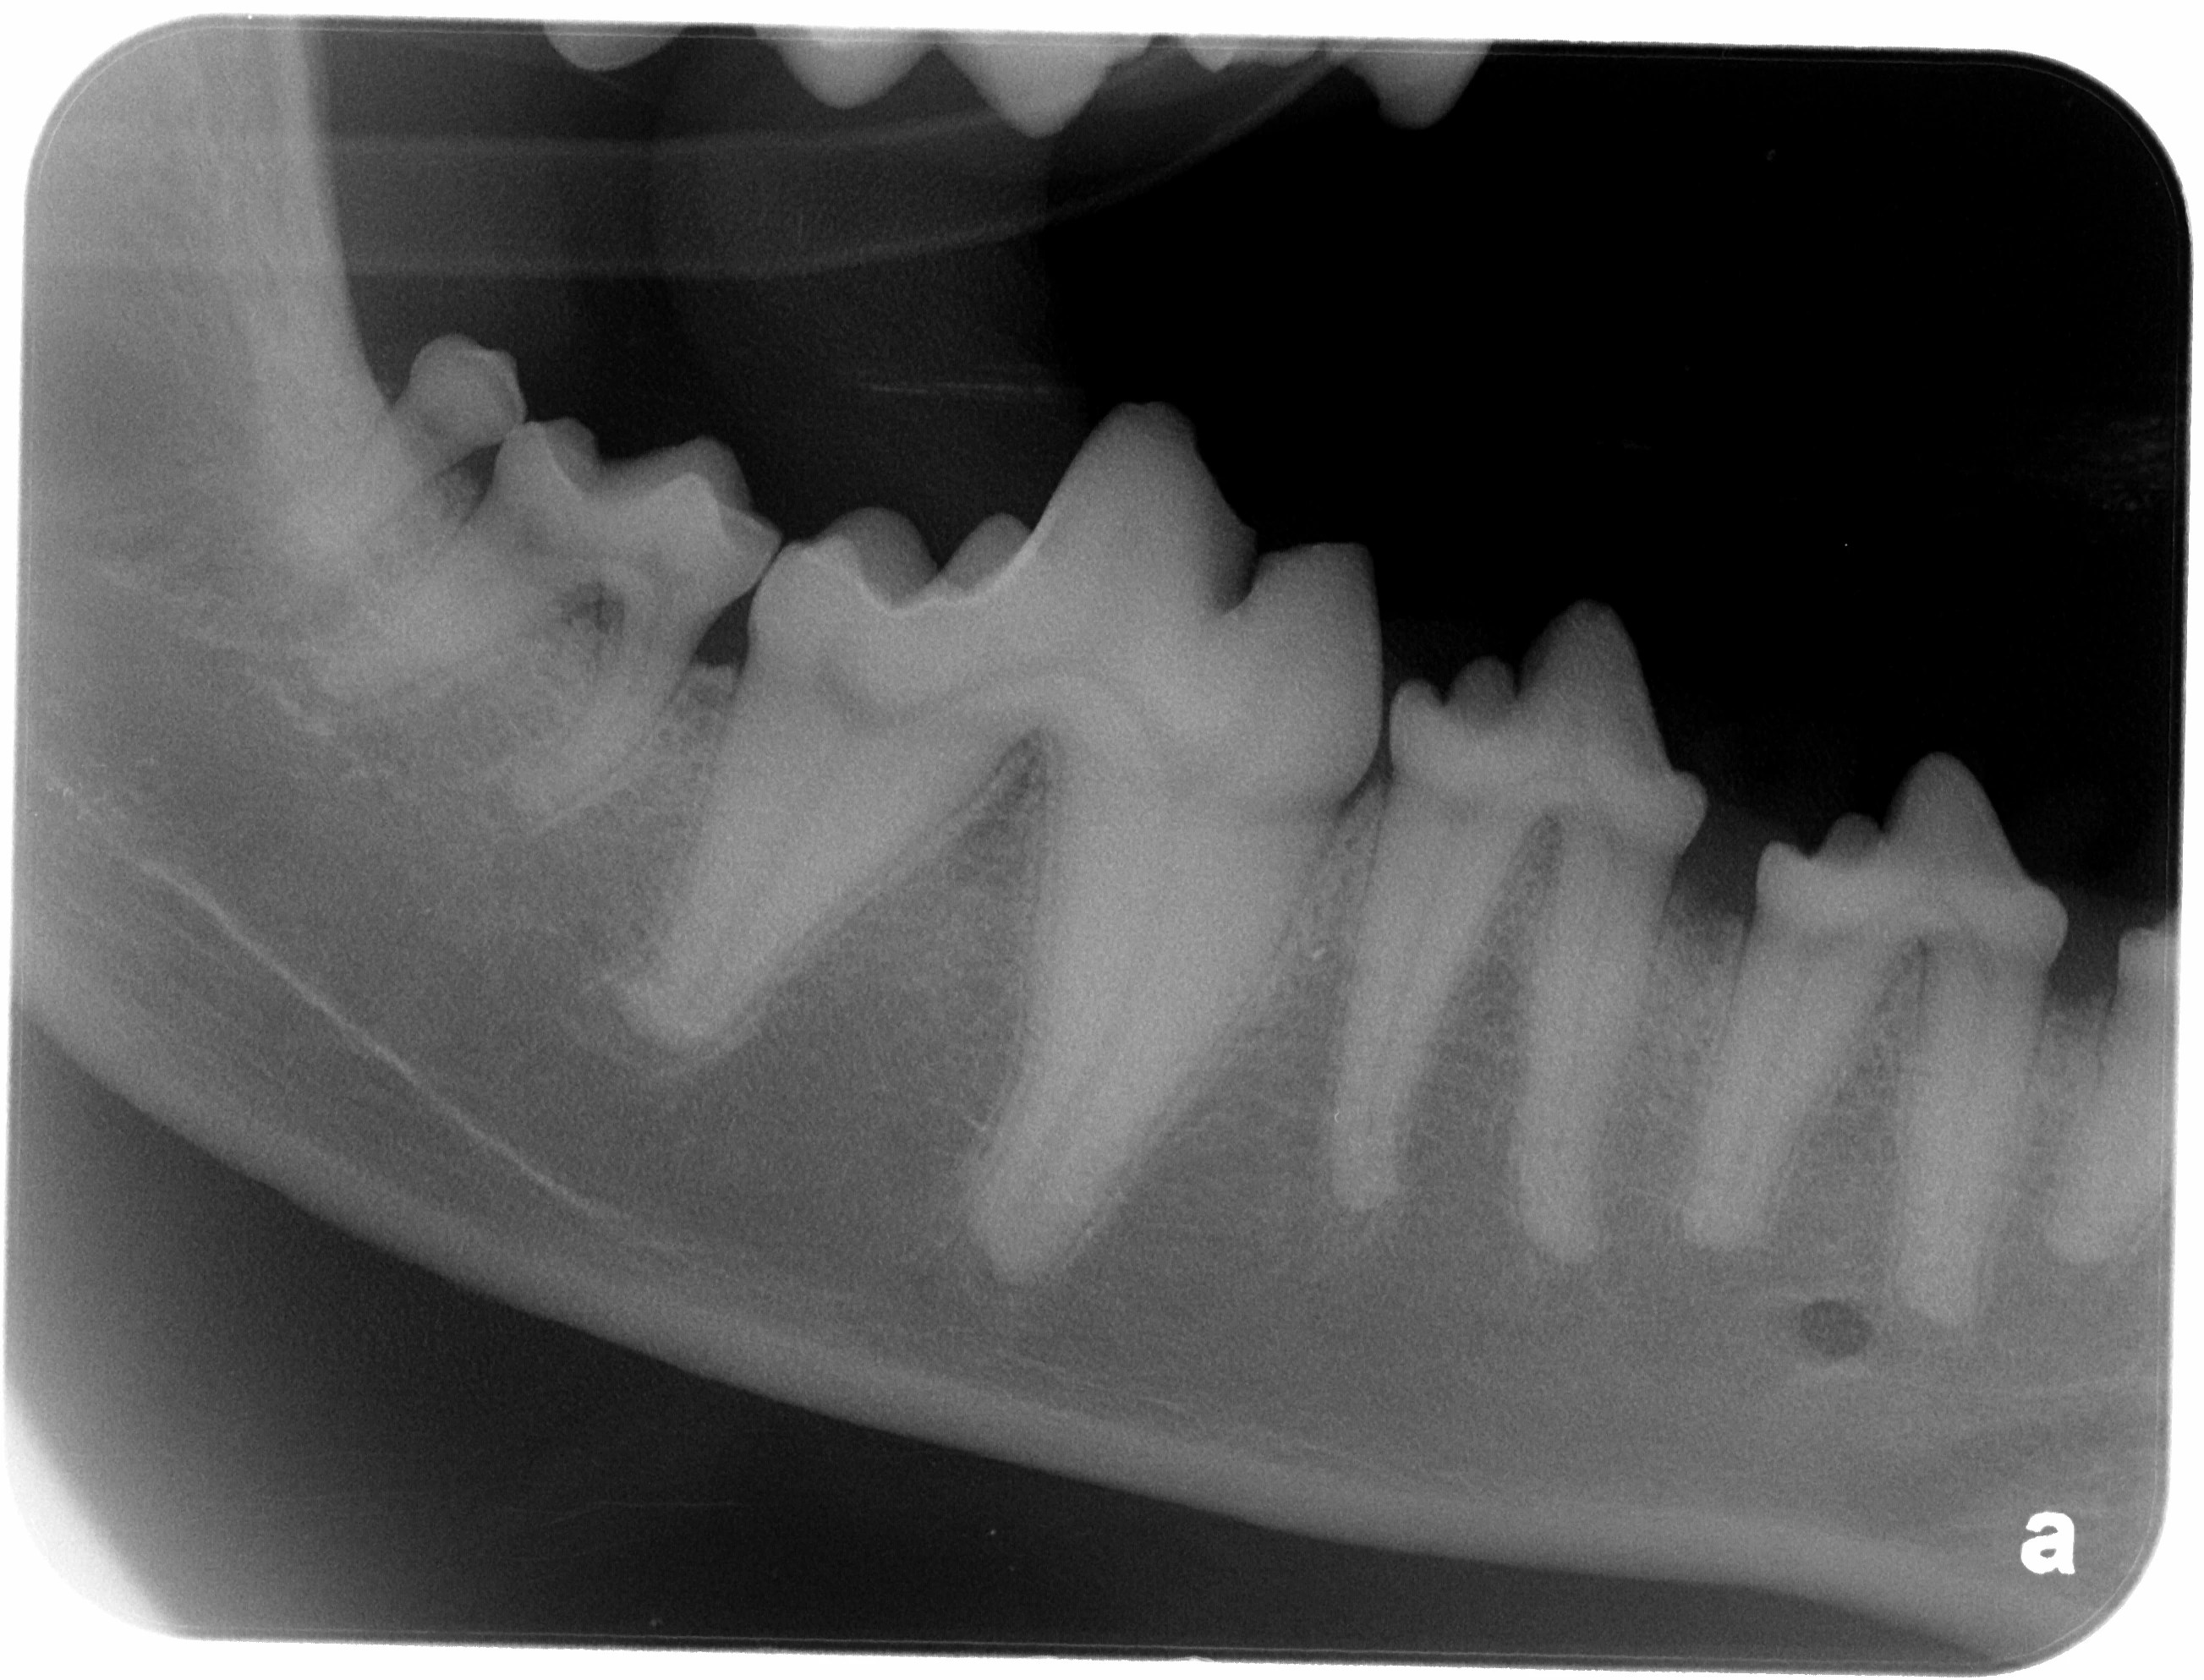

Interpretation of Dental Radiographs in Dogs and Cats, Part 1 Cat Dental X Ray This article focuses on interpretation of normal anatomic variations as well as congenital and pathologic abnormal findings on dental radiographs in dogs and cats (box 1). These units are portable or wall. Dental radiographs are absolutely critical for proper dental care in feline patients due to the potential for resorptive lesions, which are very common in cats. Both articles assume. Cat Dental X Ray.

Interpretation of Dental Radiographs in Dogs and Cats, Part 2 Normal Cat Dental X Ray This article focuses on interpretation of normal anatomic variations as well as congenital and pathologic abnormal findings on dental radiographs in dogs and cats (box 1). If extractions are needed, costs can exceed $1,000. Berg says that it used to be really hard to take dental radiographs in cats, but digital radiography has made it much easier. These units are. Cat Dental X Ray.